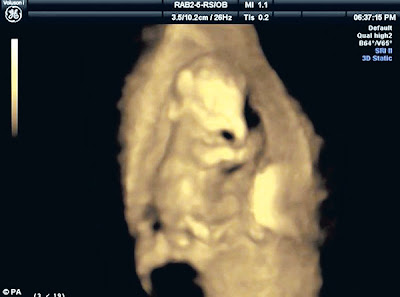

BEDFORDSHIRE – Kakitangan Zoo Whipsnade di sini, Britain merakamkan

gambar janin seekor anak gajah jantan dinamakan George di dalam perut

ibunya, lapor sebuah akhbar semalam.

Imej janin itu dirakamkan dengan menggunakan mesin pengimbas ultrabunyi

dan sebuah kamera kecil ketika kandungan ibunya berusia tiga bulan.

George dilahirkan setahun setengah selepas itu atau selepas ibunya

bunting selama 22 bulan.